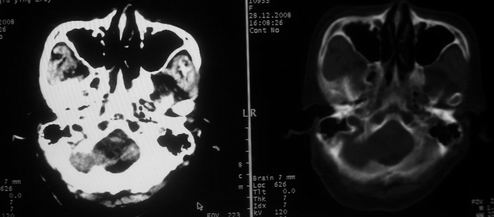

女,72岁,头晕。额骨有无问题。

额骨呈磨玻璃状增厚,考虑骨纤。

额骨呈磨玻璃状增厚,考虑骨纤

骨纤维组织异常增殖症又名纤维性骨炎,是一种以骨纤维变性为特点的骨胳系统疾病,是否为一真性肿瘤尚无定论。该病好友于儿童及青年,女性较多见,60%发生于20岁以前,偶见于婴儿和70岁以上老年人。男女发病为1∶2。80%以上表现为病骨区畸形肿胀;建议祥问病史,时间?